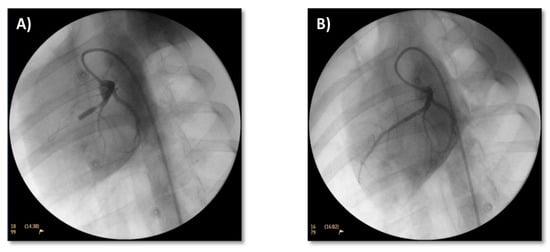

3.2. Treatment

3.2.1. Coronary Flow and ECG